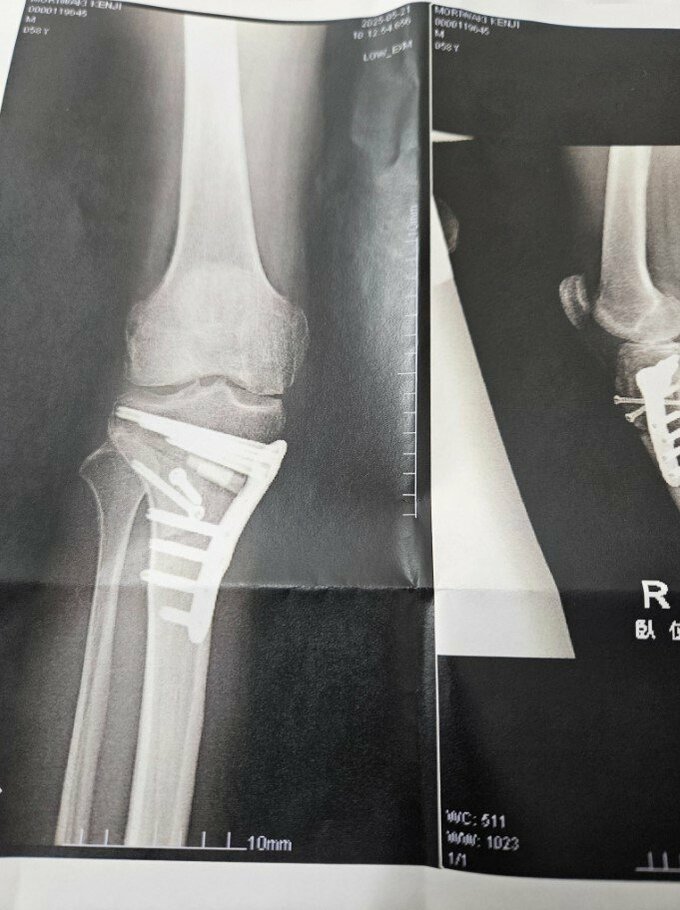

森脇さんは、数多くのマラソン大会やTBSテレビ「オールスター感謝祭」赤坂ミニマラソンなどに出場して活躍を続けていましたが、今年4月上旬に自身のYouTubeチャンネルで「大腿骨内顆軟骨損傷(だいたいこつないかなんこつそんしょう)」「内側半月板損傷(ないそくはんげつばんそんしょう)」「右ヒザがもう曲がらない」と説明し、手術を受けることを明らかにしていました。